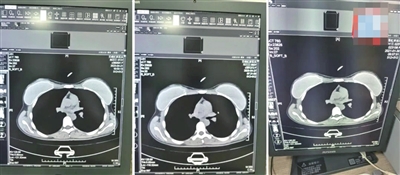

72岁的杨某某、62岁的邱某某与25岁的叶某,三人的CT片子几乎一模一样。

74岁的患者莫某在2023年4月27日拍摄了胸部和颈椎的CT,她的片子看起来和实际患者37岁的马某某在2023年11月拍的片子高度相似,片子里能直观看到项链都一模一样(红圈处)。

●有多人的片子几乎一模一样

在被举报的病历中,杨某某(72岁)和邱某某(62岁)的病历里,有根据所拍片子的情况做出的诊断,却找不到对应的影像。6月份又查到了她们的CT影像,片子上清晰看出,两位患者的吊坠形状、大小和位置都基本一致。不仅这两位患者CT影像类似,朱成刚比对发现,2021年做过CT的25岁女性叶某的片子上,也有看起来极为相似的吊坠,肉眼看,三人的片子几乎一模一样。而类似这样看上去雷同程度很高的片子,还有不少。